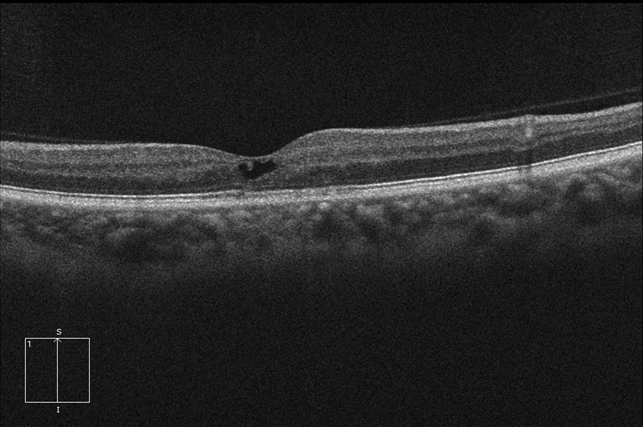

Macular Telangectasia Type 2 OCT OD - Retina Image Bank